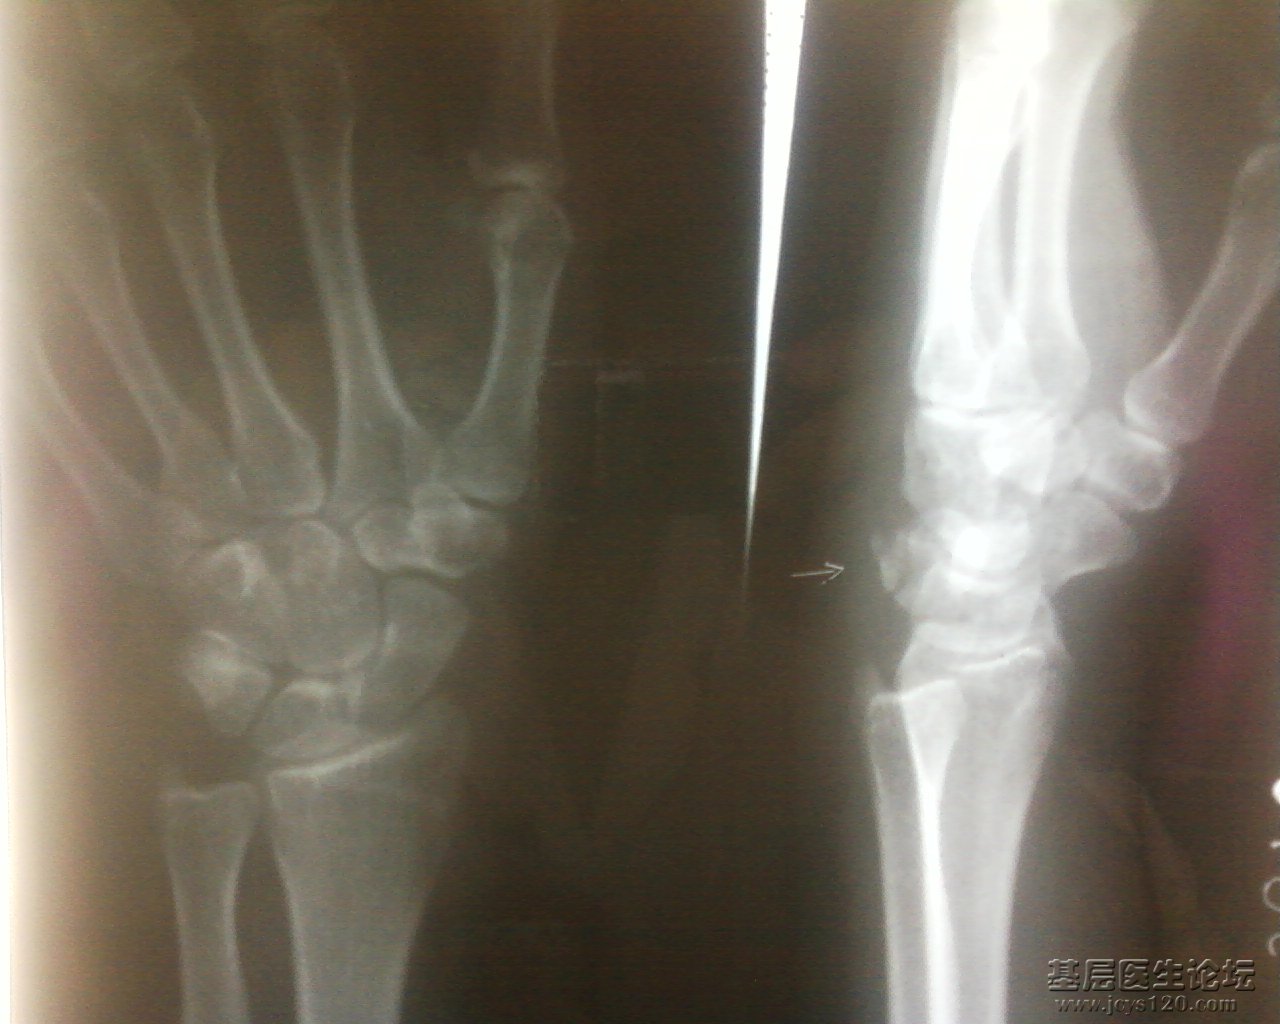

倒霉啊。先说说患者:男,14岁(有怀疑),摔伤 第一次是肩关节正位,是我一个同事照的: 显示肱骨外科颈骨折,患肢悬吊固定一周前来复查,这回是肱骨正侧位: 我照的,正位好说,侧位选取穿胸位,连续失败了 ... 阅读全文>